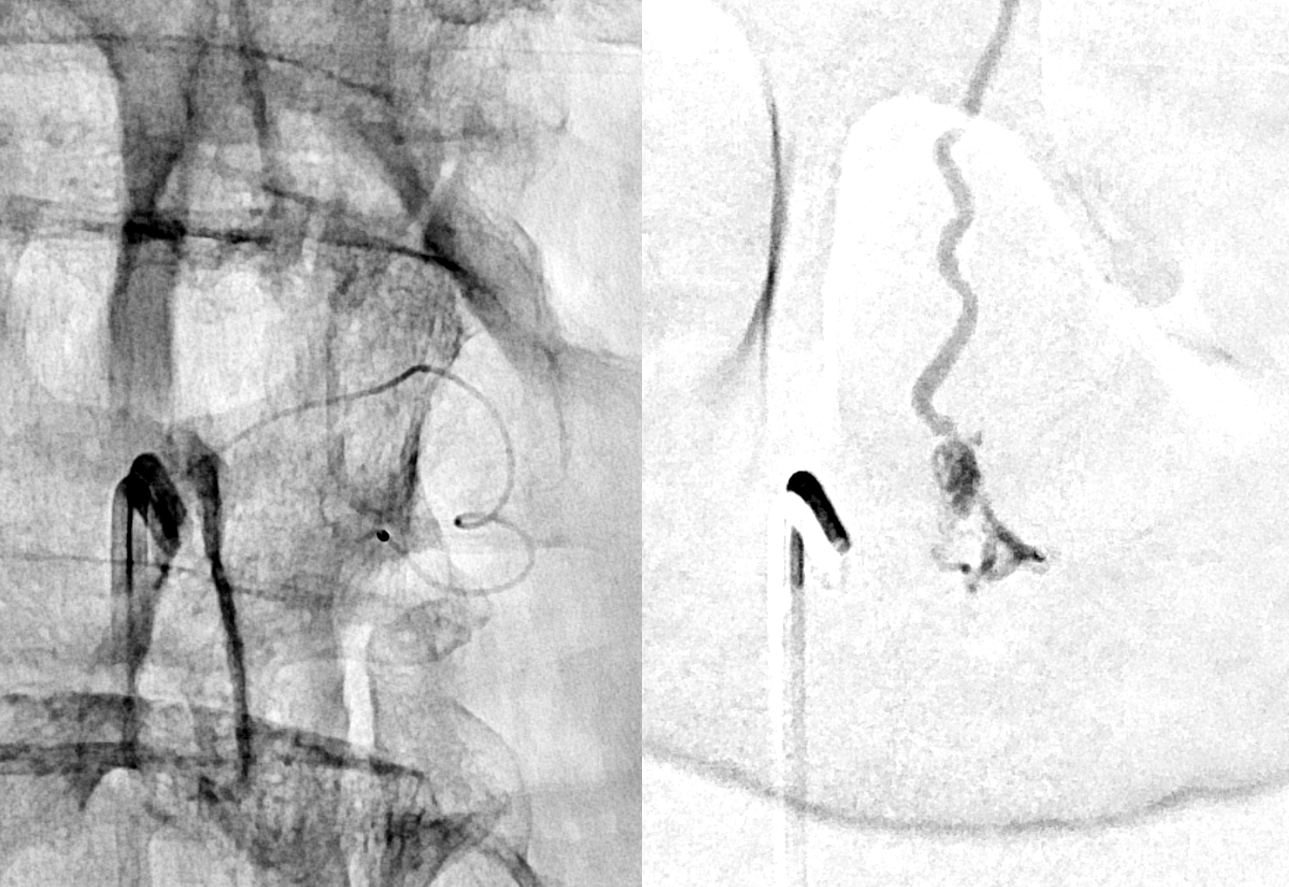

Now to treatment. Hands are raised to get optimal Cone Beam CT view of the fistula (see Cone Beam CT Comprehensive Section, particularly Spinal CBCT Page, on details of how to do this). In this case, we do a dual volume 7 second unbinned “micro” acquisition, with injection of 100% contrast at 1 cc/second for 10 seconds with 3 second delay. Reconstructions are MIP and VR

VR

Headway duo near fistula. There are several other inflows, and the position is not optimal

Below is a better position. The fistula is at the level of the ball of vessels above the microcatheter tip. Several tributaries are present, which is not great, as they will tend to polymerize nBCA before it reaches the vein. Fortunately the radicular venous segment is long, before it reaches cord surface veins, so there is a lot of safety. This is not the case with upper thoracic fistulas, and we don’t want to spill glue into cord surface veins. It promotes thrombosis, which is erroneously known as the Foix-Alajouanine syndrome. The actual syndrome was described by Foix and Alajouanine as the clinical end stage of untreated spinal dural fistulas — ascending paralysis, followed by respiratory dysfunction, aspiration, and death. It was not an iatrogenic problem. The name was adopted to describe post-treatment acute deterioration due to thrombosis of enlarged cord veins after closure of the fistula and reduction of venous flow, in part because clinical presentation is comparably horrible. Typically happens some 6-12 hours after treatment, and almost always within 24 hours. Treatment is with aggressive emergent anticoagulation, and outcome is variable.